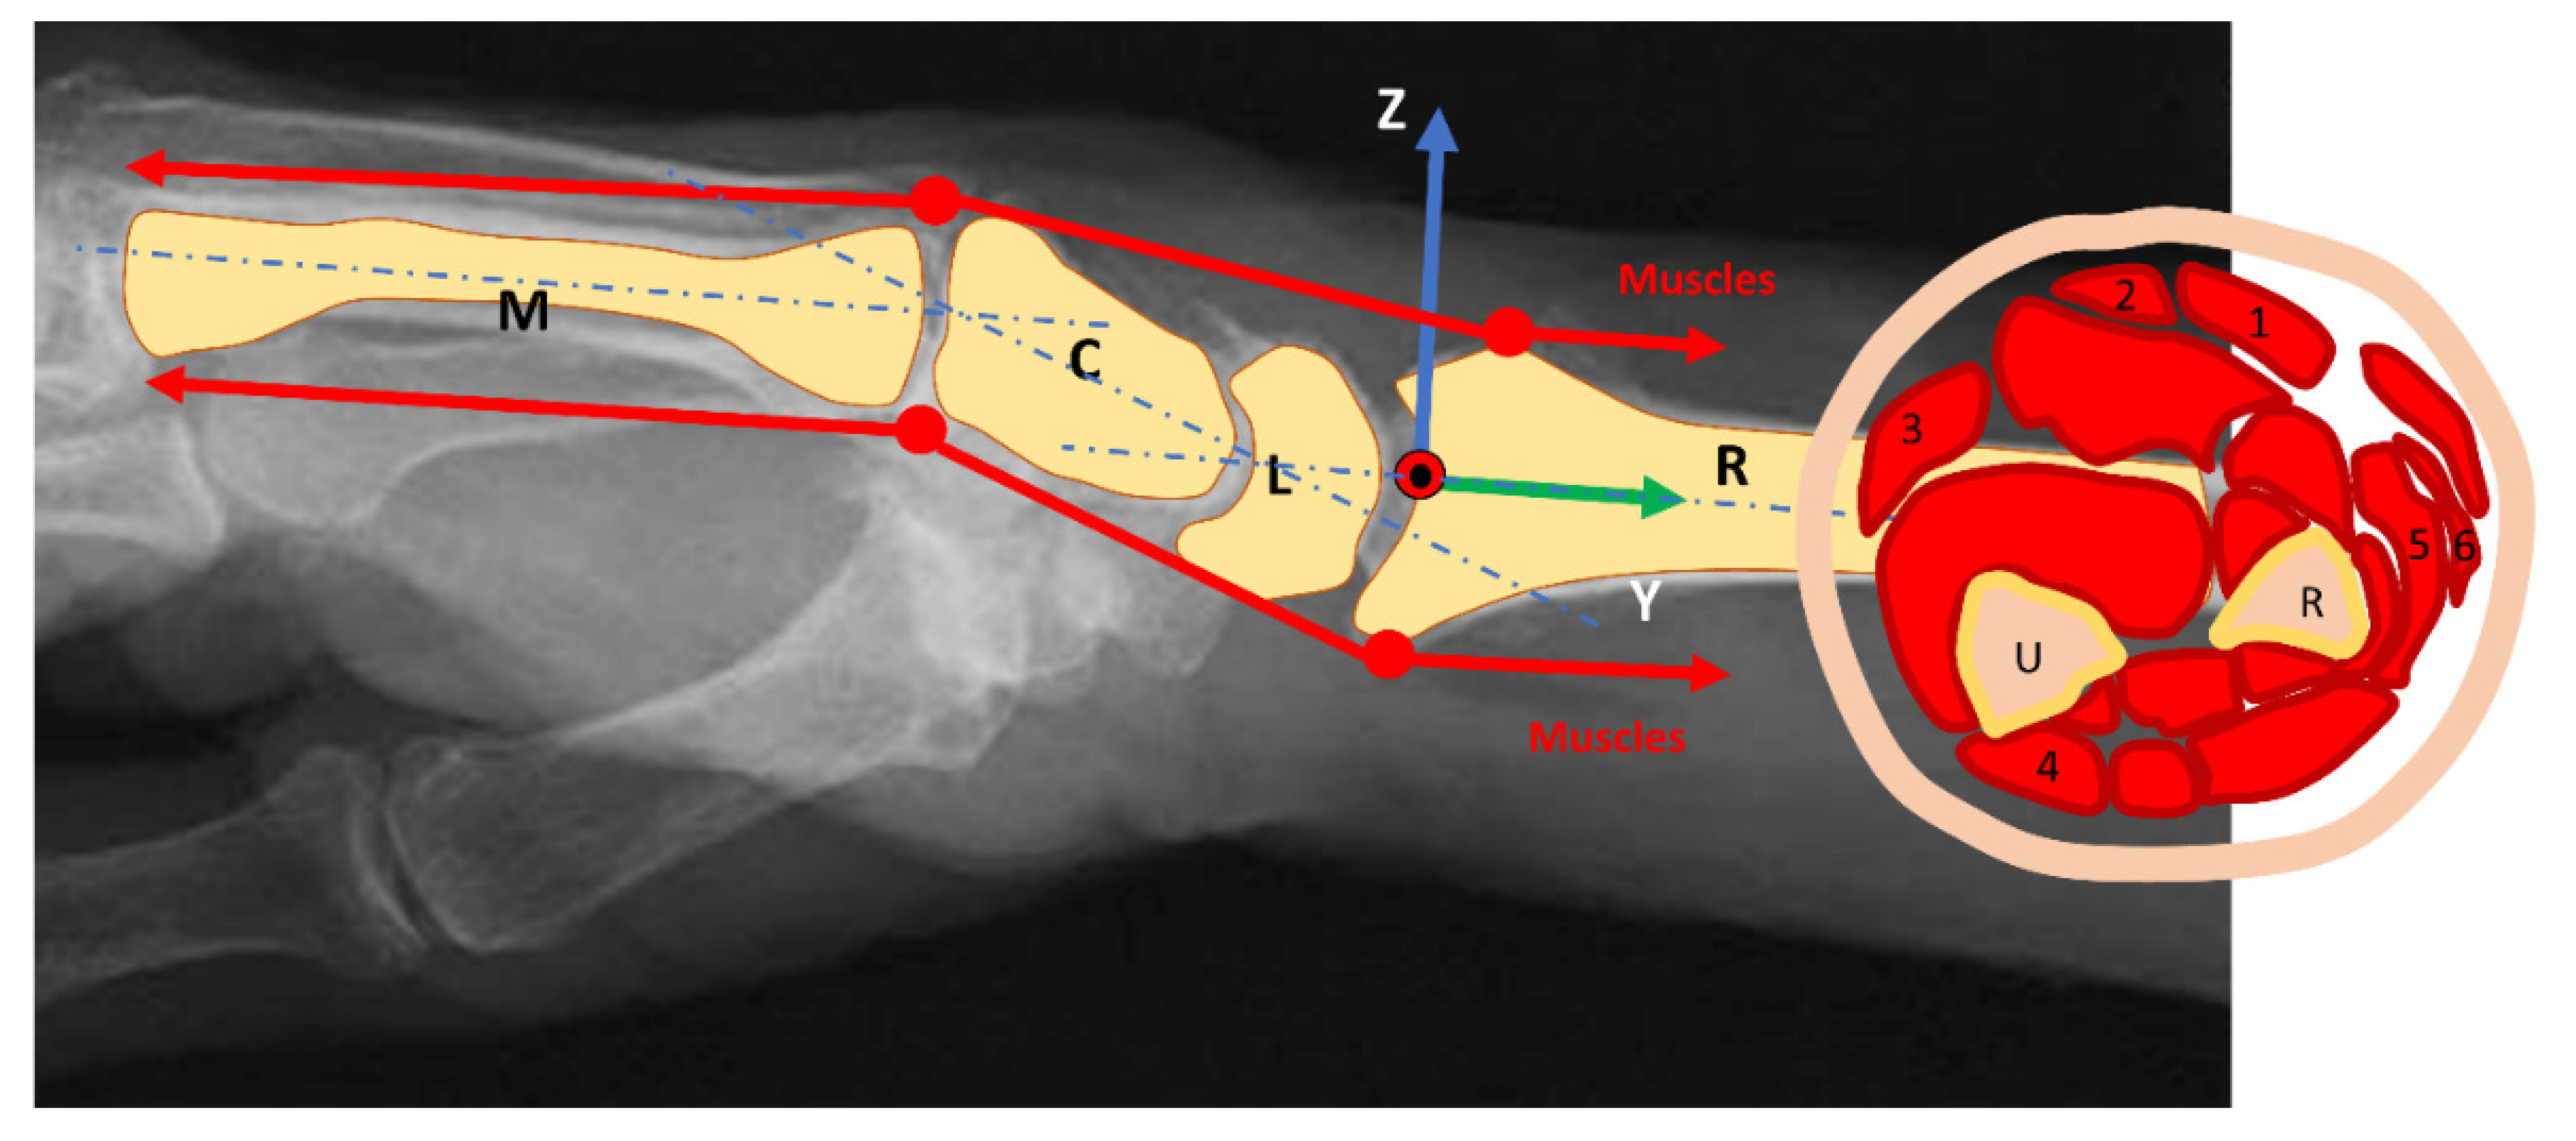

We performed a static study for the (mechanical) system composed of the forearm and wrist, assumed with negligible weight (Figure 1).

Figure 1. Muscles direction and wrist joint moment arms: The force direction is parallel to the forearm so that the physiological cross-sectional area of the muscle is the leading parameter. (1): M. flexor carpi radialis, (2): M. palmaris longus, (3): M. flexor carpi ulnaris, (4): M. extensor carpi ulnaris, (5–6): Mm. extensors carpi radialis longus et brevis; U: Ulna; R: Radius; M: Metacarpal bone; C: Capitatum; L: Lunatum.

The wrist is approximated as a perfect hinge joint for flexion and extension and radial and ulnar deviation according to the state of the art [16]. Six muscles realize the following main motion: M. flexor carpi radialis (FCR), M. palmaris longus (PL), M. flexor carpi ulnaris (FCU), M. extensor carpi ulnaris (ECU), Mm. extensors carpi radialis longus et brevis (ECRL and ECRB) [16,17,18,19,20]. The flexion is mainly produced by the PL, FCU, and FCR. The motion is supported by the flexor digitorum superficialis muscle. The extension is mainly produced by the ECRL, ECRB, and ECU. They will be assisted from the extensor digitorum muscle. The abduction muscles of the wrist (radial deviation) are the FCR, the ECRL, and the ECRB, and the abductor pollicis longus supports the motion. Muscles involved in the adduction of the wrist (ulnar deviation) are the FCU and the ECU.